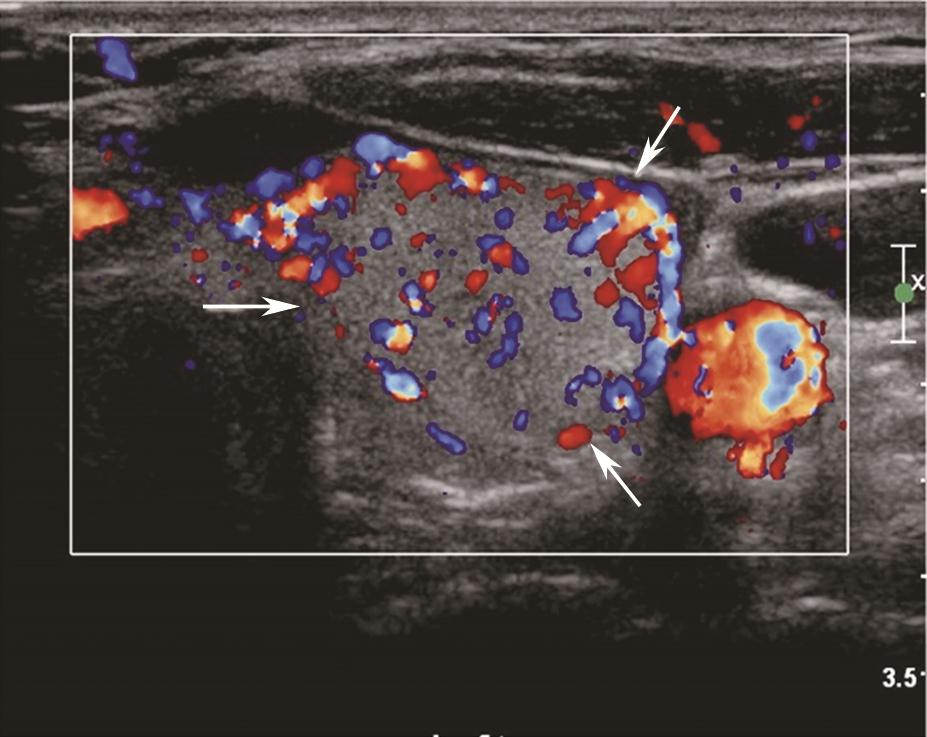

甲状腺腺瘤超声上表现为圆形或椭圆形中等回声或低回声,多伴薄声晕,肿物长轴常与腺体的长轴平行,较大者易合并囊性变、出血或坏死,内可有不规则无回声区、钙化灶或浓缩胶质,浓缩胶质表现为点状强回声后方伴“彗星尾”征,此为良性结节的特征性表现。多数腺瘤内部可见丰富规则的血流信号,周边常见较为完整的环绕血管(图7、图8)。

图7颈部正中偏左横切面:甲状腺左叶中等回声,形态规则、边界清晰,伴薄声晕(箭头所示)。T:气管;L-CCA:左侧颈总动脉

图8颈部正中偏左横切面(与图3-3-7同患者、同切面):中等回声可见丰富规则彩色多普勒血流信号(箭头所示)